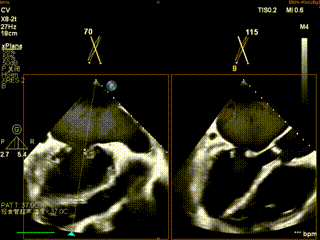

术中操作

患者在全麻状态下,经超声引导建立右侧股静脉入路,送入房间隔穿刺系统。于上下腔连线中部偏下、主动脉短轴切面中部略偏后位置尝试穿刺,多次推送穿刺针均见帐篷样隆起,但穿刺点高度均偏高,调整穿刺针位置后仍未能获得合适的房间隔穿刺高度。遂决定先于较高位置行房间隔穿刺,首次穿刺高度为6.14cm,将房间隔导丝送至左上肺静脉作为定位参照。更换房间隔穿刺系统后再次尝试穿刺,仍难以达到理想高度。

怎么上穿刺鞘攻克巨大左房伴转位穿刺难关!温医大附一院周浩教授团队创新应用“导丝定位+可调弯鞘”技术完成高难度TEER手术_https://www.jmylbn.com_新闻资讯_第12张

首次房间隔穿刺

怎么上穿刺鞘攻克巨大左房伴转位穿刺难关!温医大附一院周浩教授团队创新应用“导丝定位+可调弯鞘”技术完成高难度TEER手术_https://www.jmylbn.com_新闻资讯_第13张

首次房穿高度

怎么上穿刺鞘攻克巨大左房伴转位穿刺难关!温医大附一院周浩教授团队创新应用“导丝定位+可调弯鞘”技术完成高难度TEER手术_https://www.jmylbn.com_新闻资讯_第14张

房间隔导丝送至左上肺静脉作为定位参照

怎么上穿刺鞘攻克巨大左房伴转位穿刺难关!温医大附一院周浩教授团队创新应用“导丝定位+可调弯鞘”技术完成高难度TEER手术_https://www.jmylbn.com_新闻资讯_第15张

TEE 3D视角下房穿定位导丝

随后更换为可调弯房间隔穿刺鞘,在较定位导丝更靠前、靠下的位置进行穿刺,最终穿刺高度降至4.94cm。因患者房间隔组织异常坚韧,穿刺鞘多次尝试均未能通过,遂使用6mm外周球囊对穿刺部位进行扩张,撤处出原留置在左房内的定位导丝,随后顺利置入SGC。